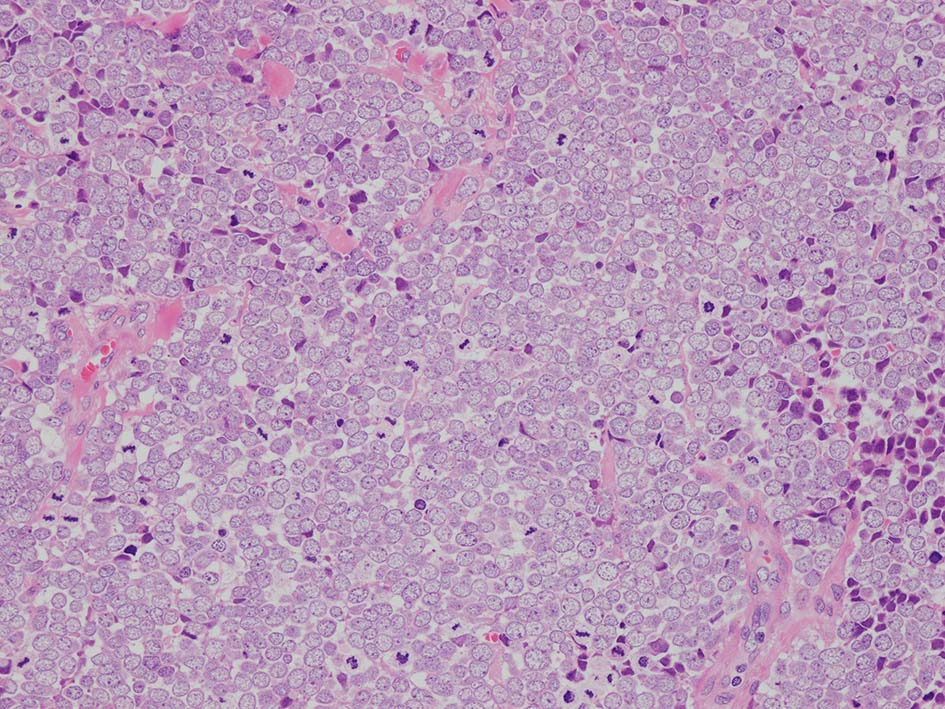

典型的な腫瘍細胞は円形, 卵円形の比較的均一な形態で「salt-and-pepper」と称される微細顆粒状クロマチンを有する小型円形核をもつ. MCPyV陽性例が均一な小型円形核を呈する傾向があり, 陰性例では, 核多形性が目立つととする報告がある.

- trabecular typeは円形から多稜形の腫瘍細胞が索状に配列, 3形のなかで腫瘍細胞がもっとも大きく, 円形核と比較的豊富な細胞質をもつ.

- small cell typeは濃いクロマチン, 多形性を示す核をもつN/C比大の小型腫瘍細胞がびまん性に増殖する.

- intermediate typeではtrabecular, samll cell typeの中間の腫瘍細胞サイズを示す. 組織型としてはもっとも多い.

HEx40

HEx200

HEx400